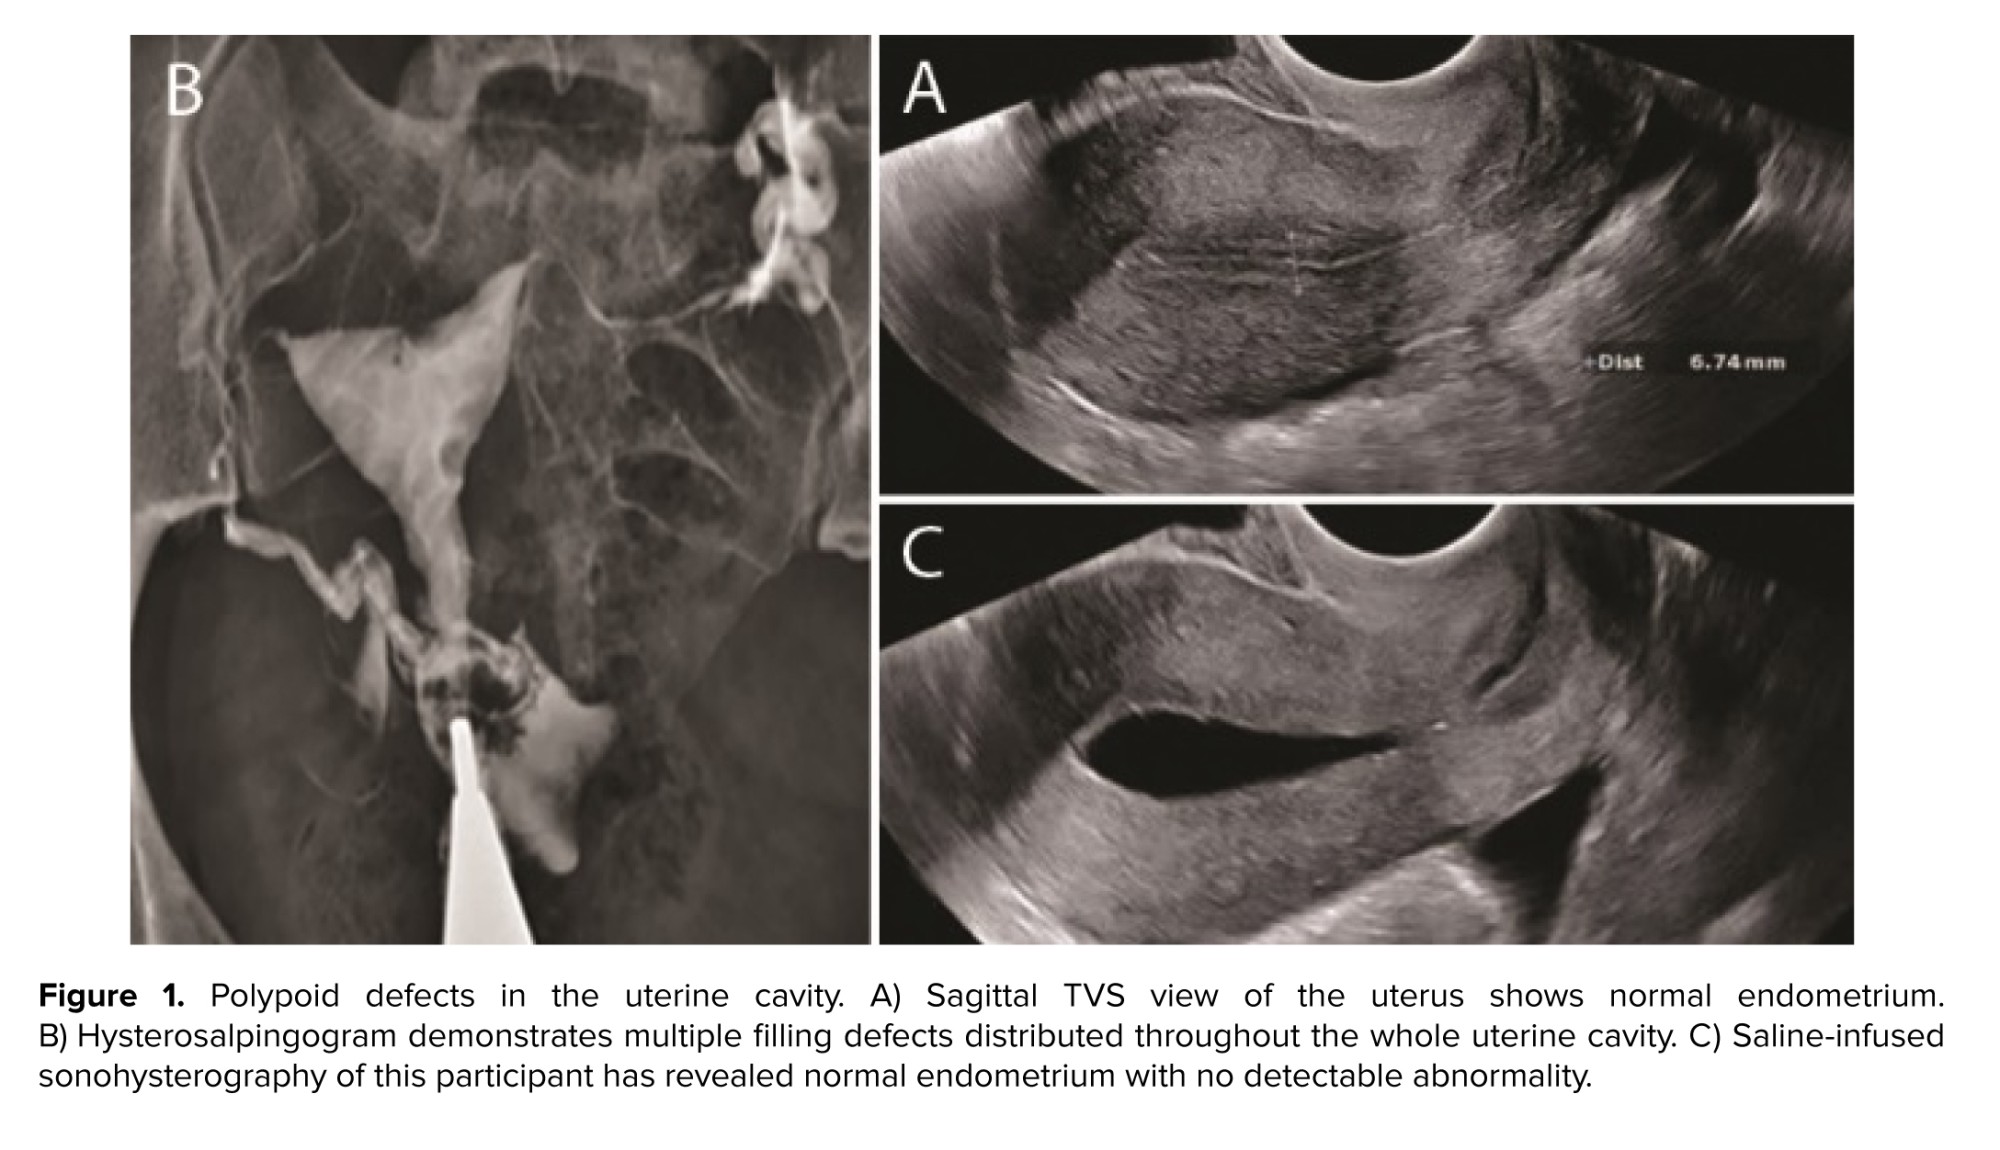

The participant denied a history of prior genital tract surgery. She did not have diabetes, hypertension, or thyroid dysfunction. She was a non-smoker with a body mass index of 28 and regular menstrual cycles. The participant’s medical record included blood test results with parameters within the normal range and a TVS report, which had been performed on day 7 of cycle, showing a normal endometrial thickness of 6 mm with a normal endometrial echo pattern and margins (Figure 1A).

The HSG performed on the participant revealed multiple filling defects throughout the uterine cavity, raising initial suspicion of polypoid hyperplasia or multiple polyps (Figure 1B). Further administration of the contrast agent induced no appreciable alteration in this HSG finding, excluding displacement of the filling defect attributed to an air bubble. The HSG showed normal findings in the fallopian tubes, with free spillage of contrast material into the peritoneal cavity. The participant was recommended for further evaluation. Next, SIS was performed, showing a normal endometrium with no evidence of polyps (Figure 1C).